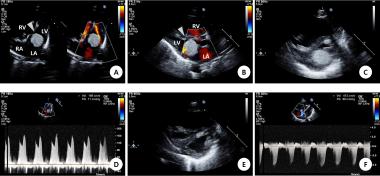

결절성 경화증 신생아에서 발생한 좌심실 유입로를 막는 심장 횡문근종의 자연적 퇴화 일례

Spontaneous regression of cardiac rhabdomyoma presenting as severe left ventricular inlet obstruction in neonate with tuberous sclerosis

Cardiac rhabdomyoma can be subclinical or have a fatal presentation according to the onset age and involving the site, size and degree of invasion. Although most rhabdomyomas become smaller with time, emergency intervention is indicated when severe obstruction induces hemodynamic instability. There is no recorded report of spontaneous resolution of huge symptomatic cardiac rhabdomyoma causing left ventricle inlet obstruction. In this report, we describe a case of spontaneous regression of large cardiac rhabdomyoma (20.5 X 15.6 mm) presenting as severe left ventricle inlet obstruction occupying 75-90 % of the mitral valve annulus in a neonate with tuberous sclerosis. Although the cardiac rhabdomyoma can be huge enough to induce LV inlet obstruction, conservative treatment without aggressive surgical intervention can be considered if the hemodymic condition does not deteriorate.